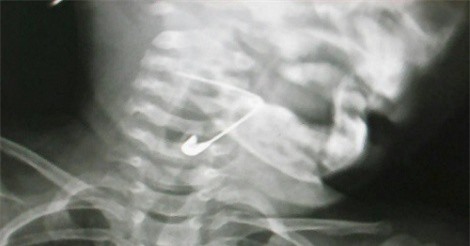

Chiều 23/8, bác sĩ Trần Công Ân, Giám đốc bệnh viện Đa khoa Vĩnh Đức (Quảng Nam) cho biết, bệnh viện vừa cứu sống bệnh nhi 18 tháng tuổi nuốt chiếc kim băng vào trong hạ họng thanh quản.